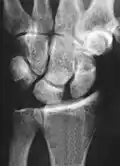

X-ray images indicate scapholunate ligament instability when the scapholunate distance is more than 3 mm, which is called scapholunate dissociation.[7] A static scapholunate instability is generally readily visible, but a dynamic scapholunate instability can only be seen radiographically in certain wrist positions or under certain loading conditions, such as when clenching the wrist, or loading the wrist in ulnar deviation.[6]

In order to diagnose a SLAC wrist you need a posterior anterior (PA) view X-ray, a lateral view X-ray and a fist view X-ray.[8] The fist X-ray is often made if there is no convincing Terry Thomas sign. A fist X-ray of a scapholunate ligament rupture will show a descending capitate bone. Making a fist will give pressure at the capitate, which will descend if there is a rupture in the scapholunate ligament.

Scapholunate ligament disruption associated with a Colles' fracture